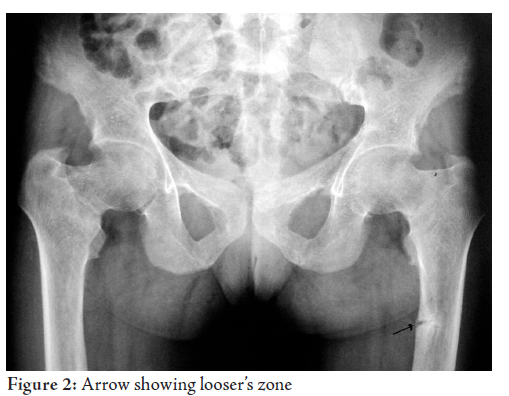

were within normal limits. Chest X ray showed normal parenchyma with looser’s

zones. (Fig. 1, 2)

Mechanical stress of the main blood vessels overlying the uncalcified cortex of

osteomalacic bones is regarded as the factor determining the location of the

symmetrical pseudo fractures.2,3

The “pseudo-fractures” typically show as transverse zones of rarefaction, varying in

width from 1 mm to 1 cm. They are multiple and generally symmetrical in

distribution, and often occur in apparently normal bone. Their distribution is

mainly ischio-pubis, ilio-pubis, femur, tibia, radius, fibula, or at the iliac

bone. 4 Other common sites are the lower

ribs and the infraglenoid region of the scapula.